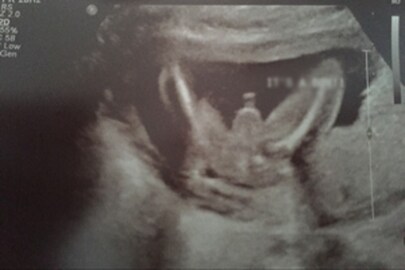

পুরুষ রোগীর ইউএসজি রিপোর্টে জরায়ু, ডিম্বনালি ও ডিম্বাশয়ের উল্লেখ ৷ রিপোর্টের জন্য নেওয়া হয় ১০ হাজার টাকা ৷ তিন দিন ভরতি থাকলেও অবস্থার উন্নতি হয়নি ৷ ইউএসজি রিপোর্টে সই রয়েছে খোদ নার্সিং হোম মালিকের ৷ ‘মহিলা’ বলে উল্লেখ থাকা ডিসচার্জ সার্টিফিকেটে সই করেন মেডিক্যাল অফিসার ৷